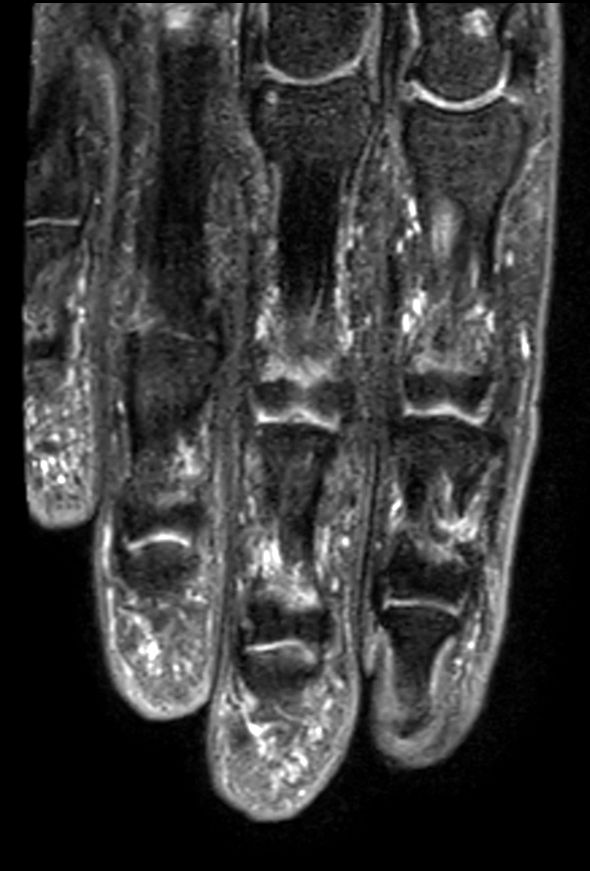

Coronal T1w TSE